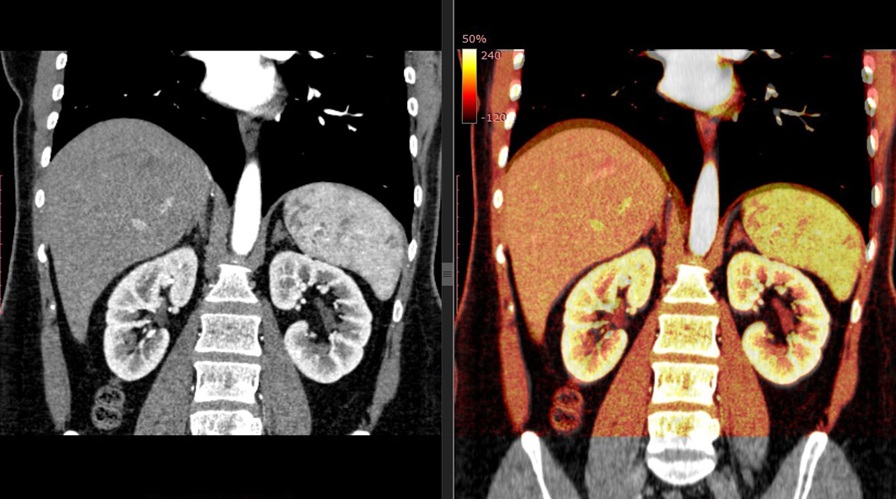

КТ с контрастом: когда необходимо

Применение контрастного вещества при компьютерной томографии надпочечников используется не всегда, но в ряде клинических ситуаций оно становится незаменимым. Контраст позволяет более чётко различать ткани с разной степенью кровоснабжения, выявлять особенности сосудистого русла и усиливать визуализацию структур, имеющих неравномерную плотность. Это особенно важно при дифференциации опухолей: злокачественные новообразования обычно накапливают контраст активнее и медленнее его выводят, в отличие от доброкачественных образований, таких как аденомы.

Контрастное усиление показано в тех случаях, когда на обычных снимках наблюдаются образования неясной природы, при подозрении на феохромоцитому, при подготовке к хирургическому вмешательству или при поиске метастазов. Также оно используется для оценки степени васкуляризации опухолей, выявления некротических участков или воспалительных изменений. Введение контрастного вещества позволяет получить серию снимков в разные фазы кровотока, что повышает информативность исследования и помогает избежать ошибок при интерпретации.

Решение о необходимости введения контраста принимает врач, учитывая клинические показания, анамнез пациента и результаты предыдущих исследований. Хотя контрастные вещества в большинстве случаев переносятся хорошо, пациенту может быть рекомендовано предварительное обследование функции почек, чтобы исключить возможные осложнения. Также при наличии у пациента аллергии на йодсодержащие препараты проводится дополнительная подготовка или выбираются альтернативные методы диагностики. Несмотря на дополнительные расходы и возможный дискомфорт, контрастное усиление значительно расширяет диагностические возможности КТ и позволяет врачам диагностических отделений Санкт-Петербурга принимать более точные и обоснованные решения.